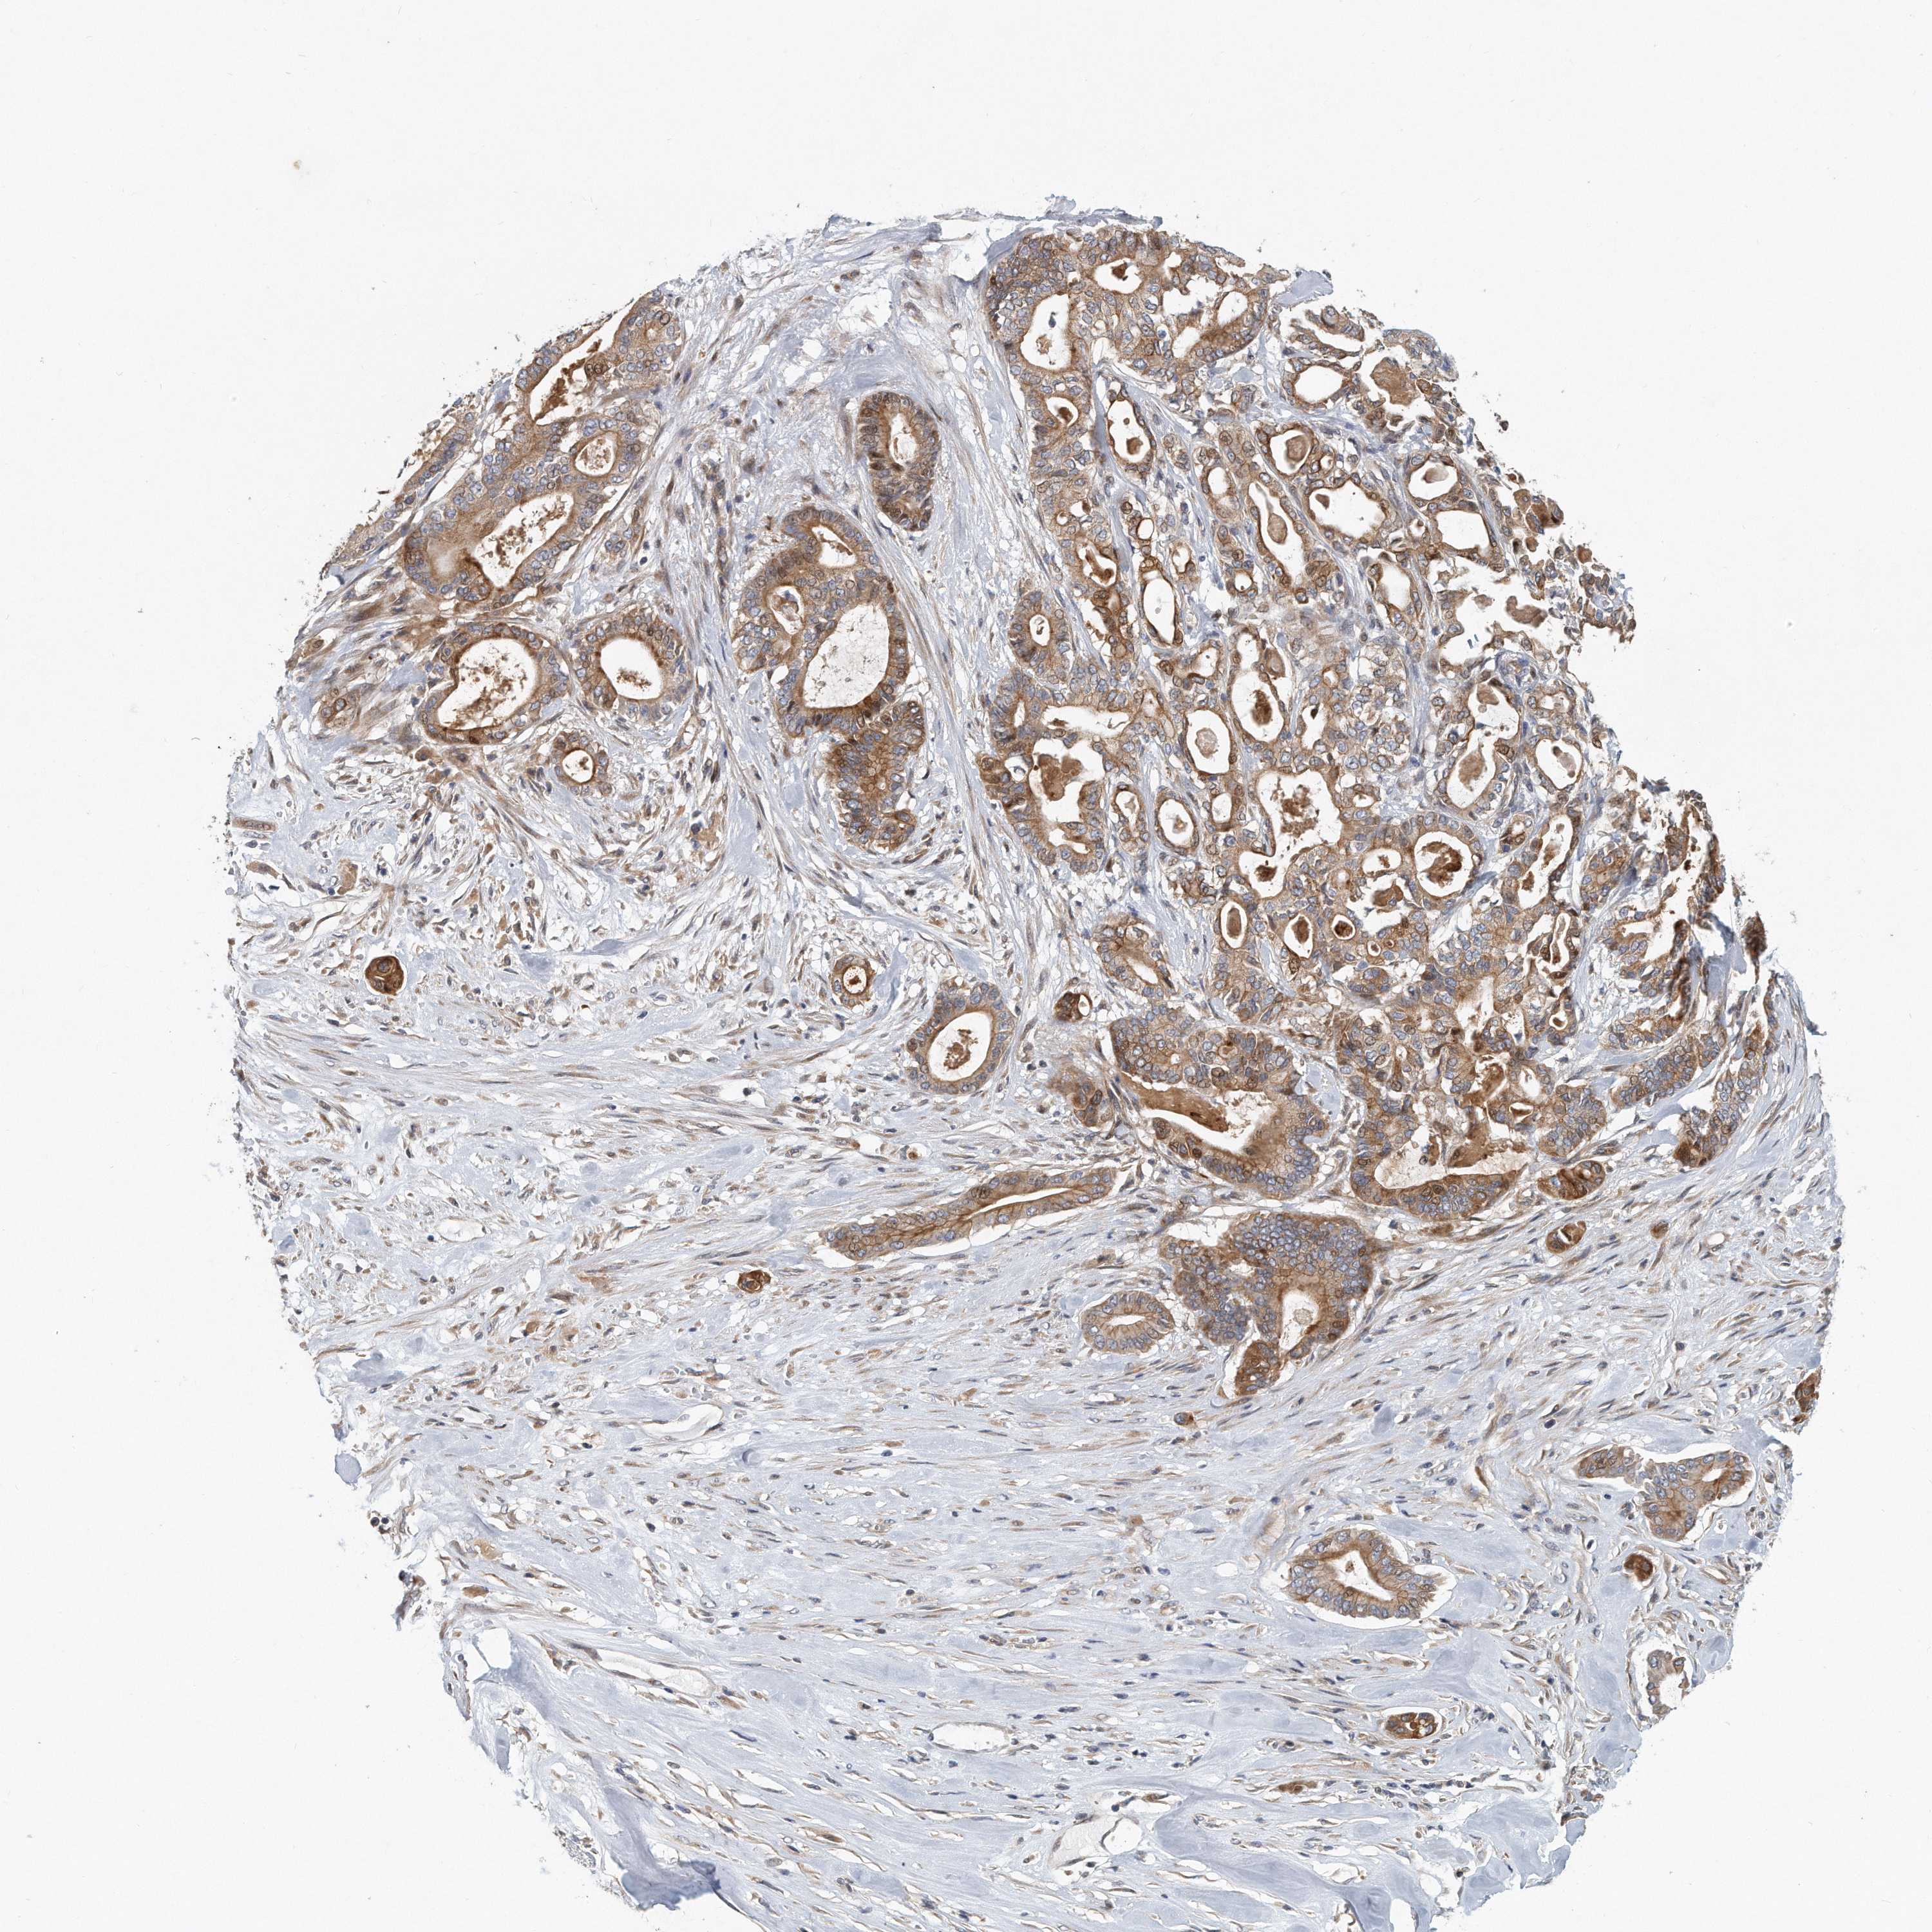

PANCREATIC CANCER - Protein expressioni

A mouse-over function shows sample information and annotation data. Click on an image to view it in a full screen mode. Samples can be filtered based on level of antibody staining by selecting one or several of the following categories: high, medium, low and not detected. The assay and annotation is described here.

Note that samples used for immunohistochemistry by the Human Protein Atlas do not correspond to samples in the TCGA dataset.

Antibody stainingi

Antibody staining in the annotated cell types in the current human tissue is reported as not detected, low, medium, or high, based on conventional immunohistochemistry profiling in selected tissues. This score is based on the combination of the staining intensity and fraction of stained cells.

Each image is clickable and will lead to virtual microscopy that enables deeper exploration of all samples and also displays staining intensity scores, fraction scores and subcellular localization as well as patient and tissue information for each sample.

Antibody HPA010509

Staining

High

Medium

Low

Not detected

Intensity

Strong

Moderate

Weak

Negative

Quantity

>75%

75%-25%

<25%

None

Location

Nuclear

Cytoplasmic/membranous

Cytoplasmic/membranous,nuclear

Adenocarcinoma, NOS